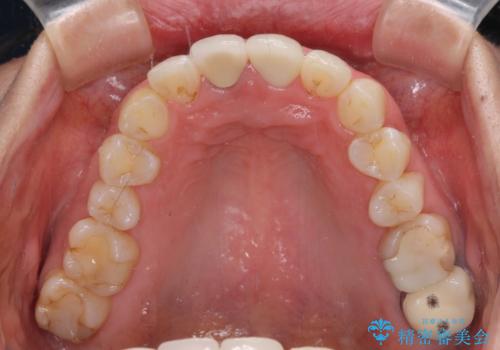

目立つ前歯の詰め物 オーダーメイドのセラミッククラウンで審美的に仕上げる

- 前歯のプラスチックが変色していることを気にして来院された患者様です。

反対側同名歯にセラミッククラウンが装着されていたため、そちらのクラウンと形態や色彩を揃えるようオーダーメイドタイプのオールセラミッククラウンにて補綴することとしました。

2本同時に処置をし、2本とも明るい色合いにすることをお勧めしましたが、今回は1歯のみとしました。

左右のバランスが取れ、患者様には大変満足していただきました。